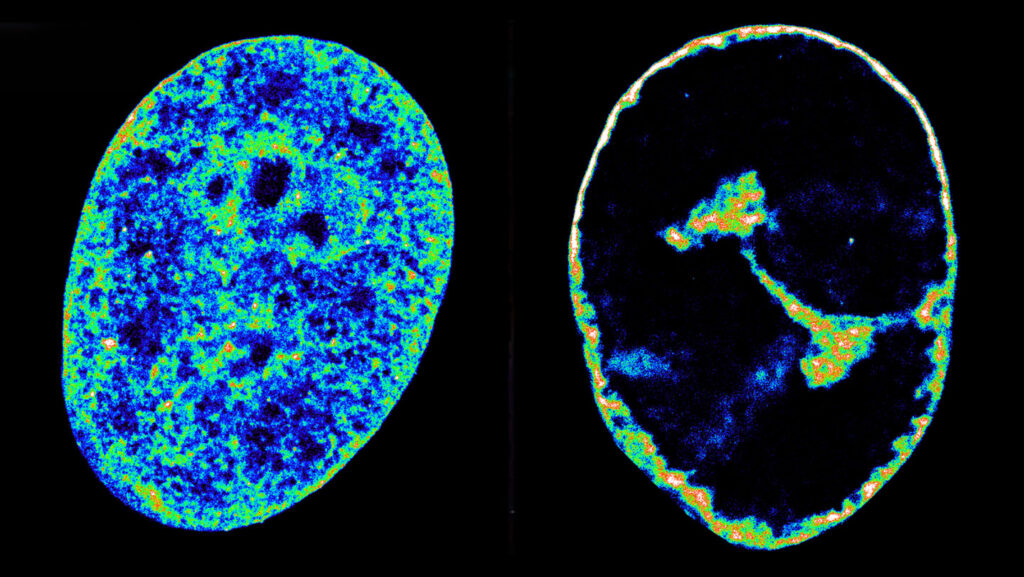

Scientists have observed that when HSV-1 infects our cells, our chromosomes begin to warp and condense, shifting to the periphery of the nucleus to make space for the virus’s many copies. It has been unclear whether this process is intentional or simply a by-product of the virus’s invasion. “We’ve never had the technology to image cells at a fine enough resolution to look closer,” says Maria Pia Cosma, a synthetic biologist at the Centre for Genomic Regulation in Barcelona.

Advances in super-resolution microscopy have now made this possible. Cosma and her colleagues were able to image cells up to eight hours post-infection, including structures just 20 nanometers wide.

The scientists found that within an hour of infection, HSV-1 co-opts two genes — RNA polymerase II (RNAP 2) and DNA topoisomerase (TOP1) — that compact the host’s chromatin into super-dense bundles. Chromatin is the DNA-protein complex that, when condensed, forms our chromosomes. The virus then reshapes the architecture of the chromatin, similar to folding origami, to bring itself into contact with loops of DNA containing the host genes needed for viral replication.